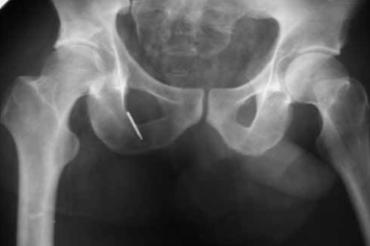

В случае отказа больного от аппарата внешней фиксации или при противопоказаниях производится скелетное вытяжение сроком 3-4 недели. Когда отломок проецируется на уровне или ниже ориентирной линии (рис. 4), разрез производится на 1 см ниже ее. Также тупо разводятся волокна большой ягодичной мышцы.

Рентгенография тазобедренного сустава до и после вправления. Перелом среднего отдела заднего края вертлужной впадины со смещением